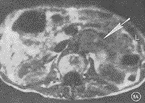

图4 恶性功能性副节瘤 CT强化示肾前区肿瘤不均匀强化(大箭头),肿瘤侵犯腰椎骨质(小箭头)

2.2 病变数目:本组14例均为单发,未见多发。其中呈团块结节者10例(图1,2,5,6),呈连续长块状4例(图4)。

2.3 病变大小:病变最大径<5 cm者6例(图1,2,5,6),其中良性5例,恶性1例;功能性5例,非功能性1例。病变5~10 cm者5例(图3),其中良性4例,恶性1例;功能性1例,非功能性4例。病变>10 cm者3例(图4),均为恶性;功能性1例,非功能性2例。

2.4 病变形态:病变边缘呈光滑圆形结节状3例,均为良性(图1,2,6),有不同程度分叶切迹,或呈分叶不规则状11例(图3,4,5)。

2.7 病变质地:病变密度或信号强度呈均匀者7例(图1,5),不均匀者2例(图2),有明显坏死囊变者5例(图3,4),其中1例有小点钙化。伴有坏死囊变者5例中4例为恶性,1例为良性。

2.8 病变强化特点:5例进行CT强化扫描均表现肿瘤周边部明显强化(图6),其中3例肿瘤内部见不规则强化,2例良性(图2),1例为恶性(图4)。

2.9 病变侵犯特点:14例中10例表现肿瘤压迫周围组织移位;4例侵犯周围组织均为恶性,其中1例伴骨侵犯(图4)。